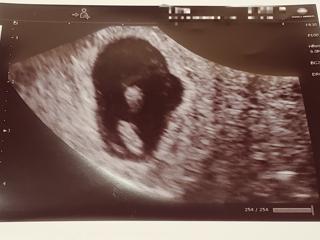

第二子妊娠。6w1dで心拍の確認ができず不安な1週間を過ごしましたが、今回無事確認できてなんとかここまできました。赤ちゃんは7mmはあるとのことで順調だそうです。

自然妊娠なのですが今回で4回目の妊娠で、流産を予防する為にダクチルを服用しています。

葉酸サプリも妊娠前から夫婦で飲んでいたしビタミンDも大事だと知って摂取しているので、何とか無事出産できますように。